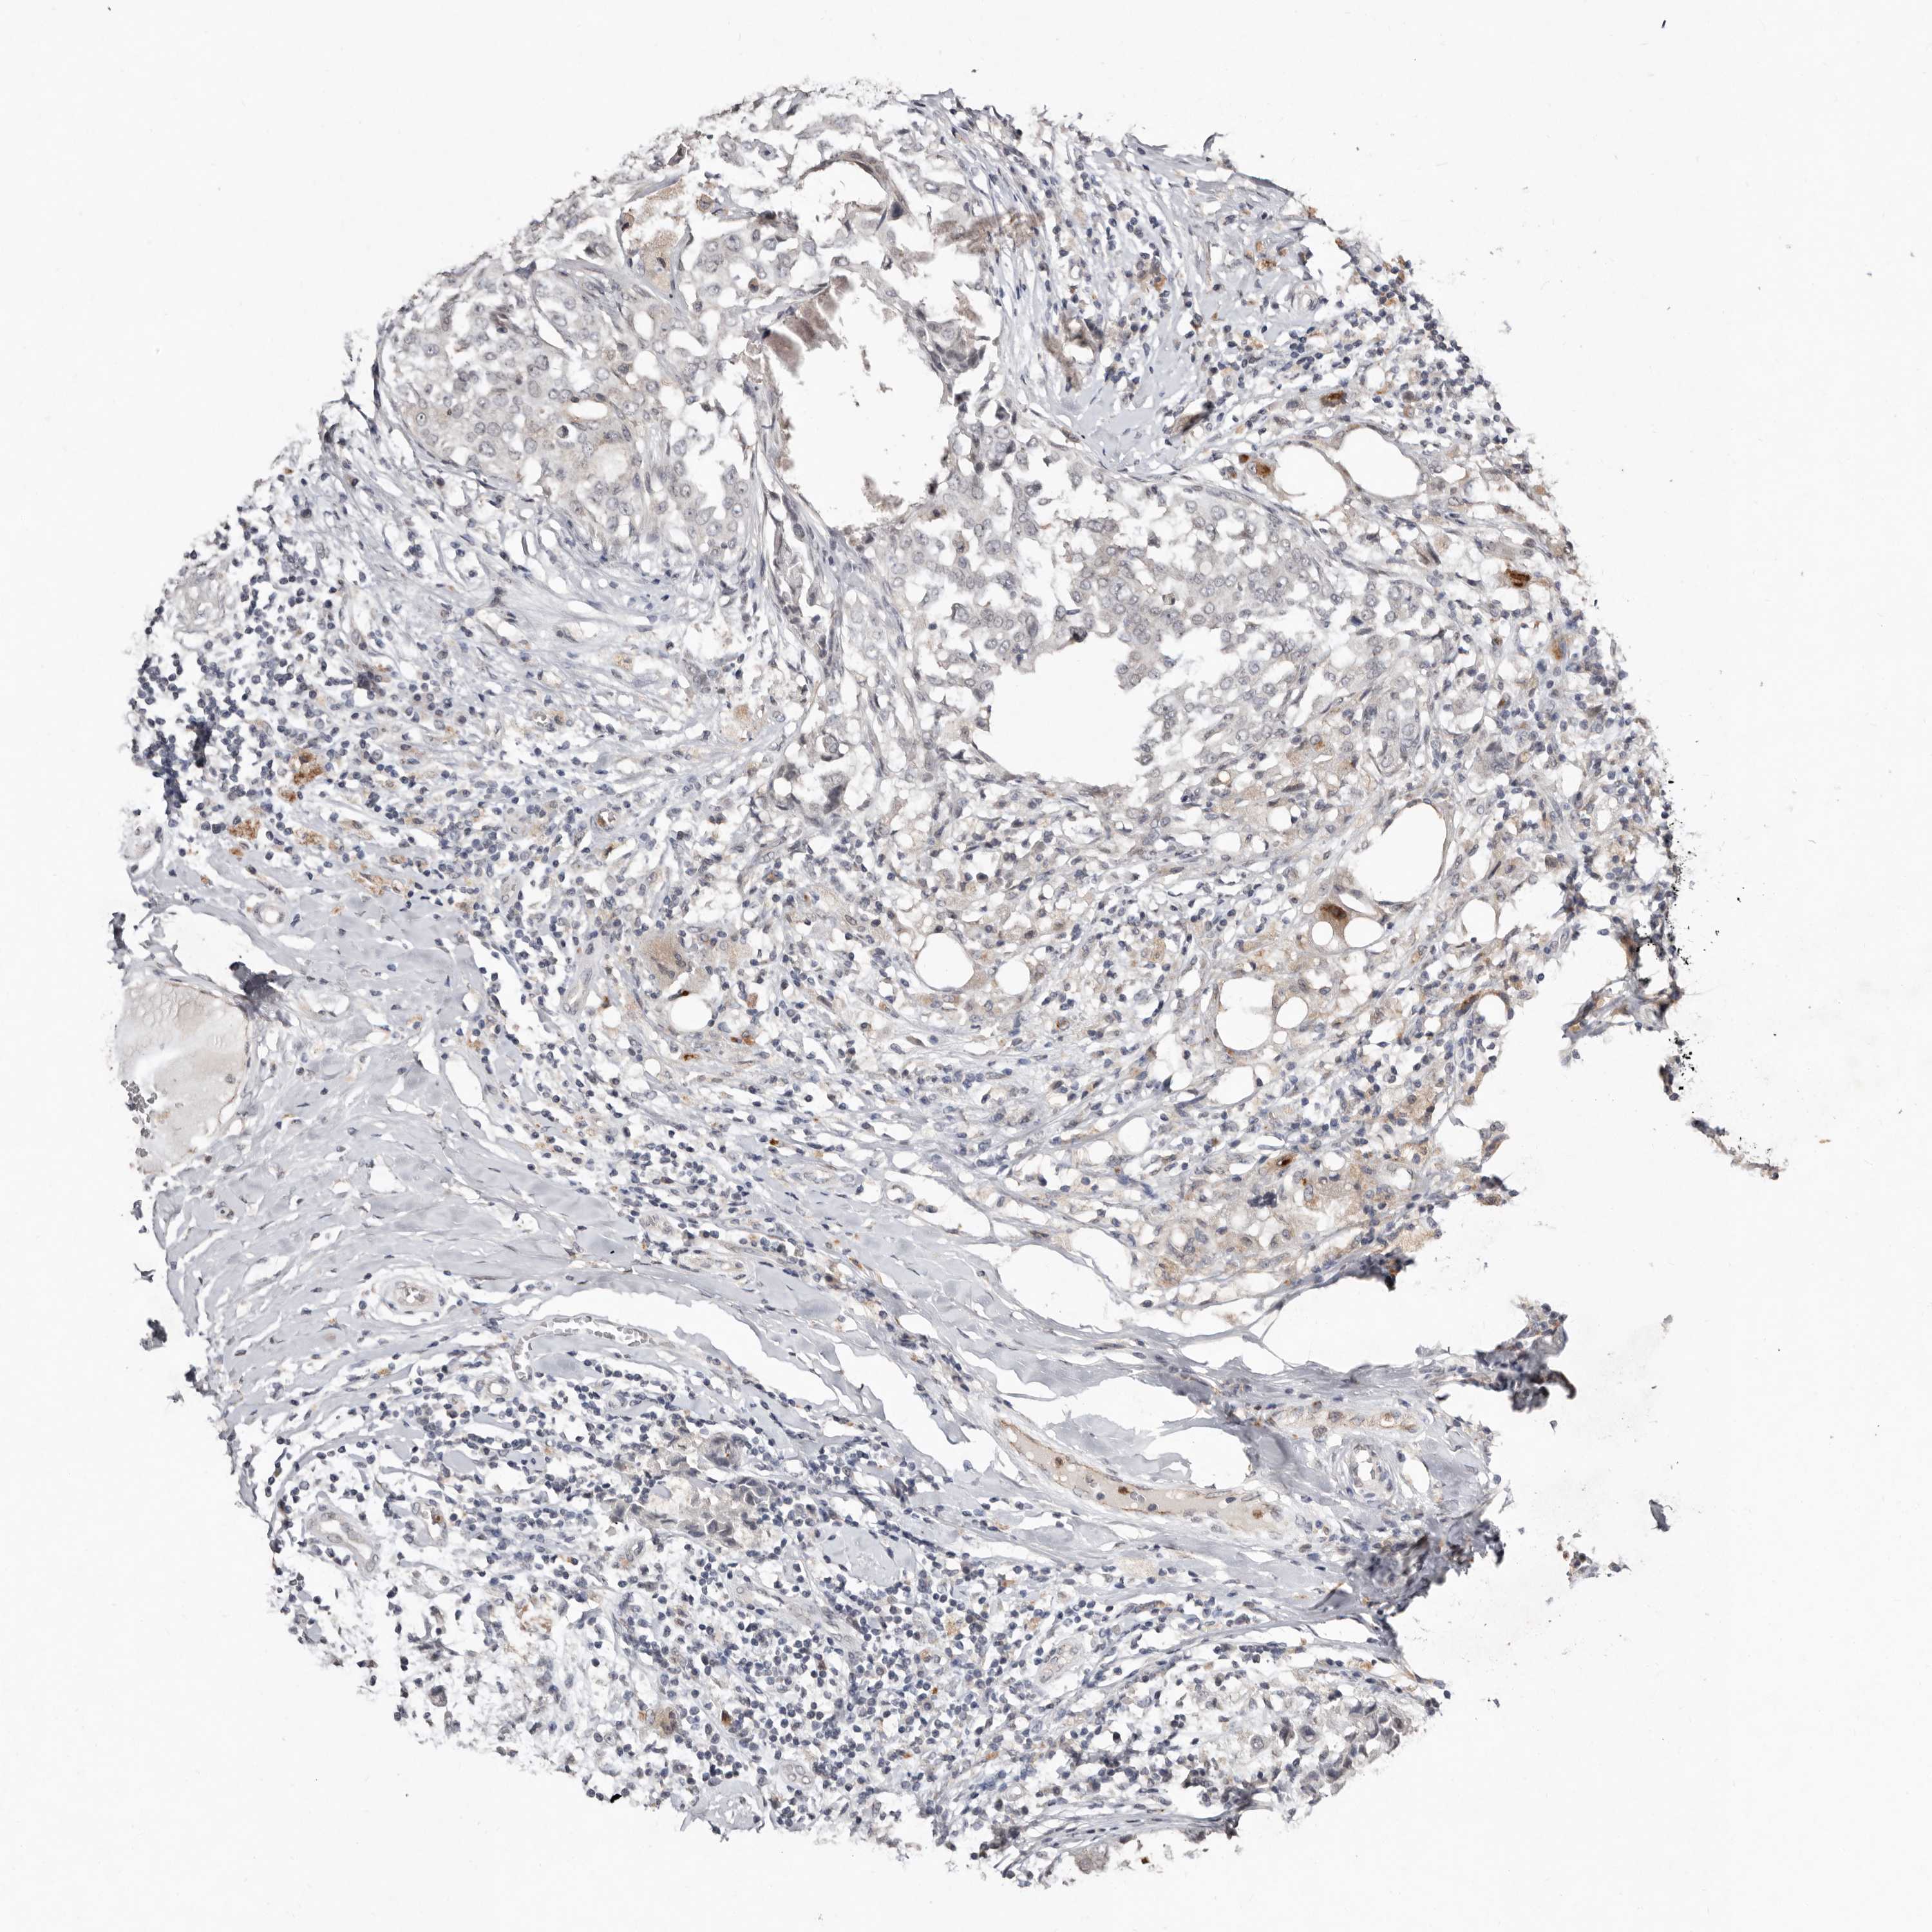

CANCER BREAST CANCER Show tissue menu

BRCA TCGA BRCA VALIDATION PROTEIN EXPRESSION

SULT1E1 is not prognostic in Breast Invasive Carcinoma (TCGA)

Average pTPM 0.5

Number of samples 1022